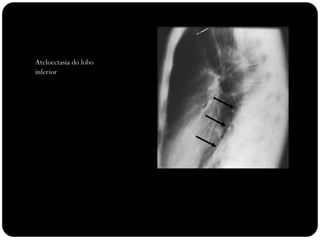

Atelectasia do lobo

inferior esquerdo

Atelectasias de lobos

inferiores deslocam

o hilo posterior e

medialmente;

Ateloectasia do lobo